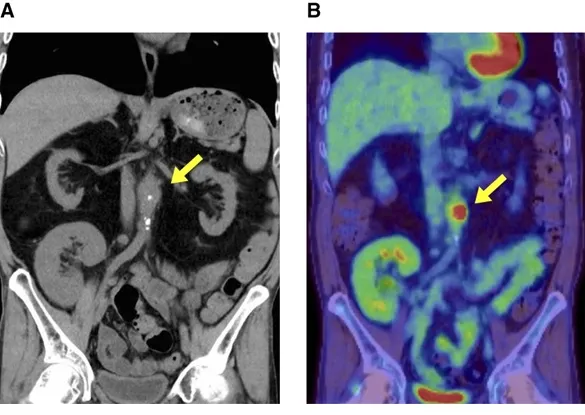

1. TC abdominal no 6º dia de investigação, sendo identificado um abaulamento focal da parede anterior da aorta abdominal com calcificação e “borramento da gordura peri-aórtica.

2. PET/CT (16º dia): Captação de FDG no mesmo local, confirmando inflamação ativa – diagnóstico: aortite infecciosa por Salmonella.

Achados de imagem na aortite infecciosa. (A) TC no 6º dia mostra abaulamento focal e calcificação da parede anterior da aorta abdominal, próxima à artéria mesentérica superior, com borramento da gordura ao redor (sinal de inflamação). (B) A PET/TC no 16º dia evidencia captação de fluorodeoxiglicose (FDG) na mesma região, indicando inflamação ativa.